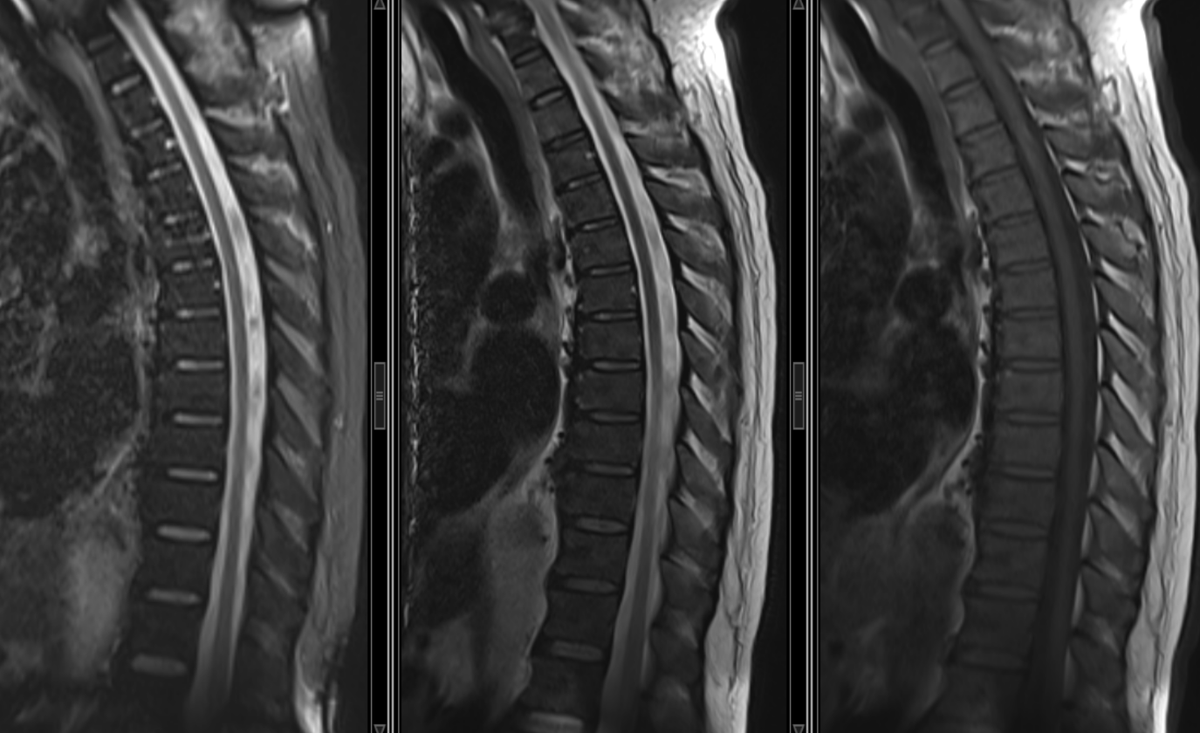

Nice one, but without the axial images, it’s hard to get the dissected aorta.. you wrote there are no herniated disc, so I am wondering what was the reason for getting the enlightening axials

Exactly. Without the axial slices... great chances of missing it. That’s why axial images should span the entire spine when youn don't see nothing (like disc pathology) at the sagittal

- Aortic dissection + pleural effusion